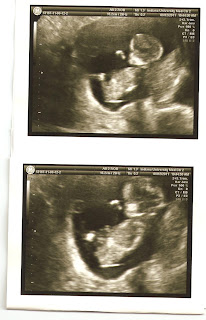

So yes, if you couldn't hear it....the news is that I'm pregnant!  We're 13 weeks now, and everything is going just fine.  The picture I attempted to show in the video is actually right here:

As you can see, the little baby is just kind of lounging in mom right now.  We got to hear the heart beat, and I can't believe how much he/she has changed since our first ultrasound.  I haven't really started showing just yet, and no, I don't think I'll be posting those pictures of my bump, but that's mostly because honestly, right now, I just feel fat.  But, I did buy my very first maternity clothes this last weekend because Nain's normal clothes just aren't cutting it right now.  I may keep these pants around for occasions like Thanksgiving, etc., because damn, they are comfortable.